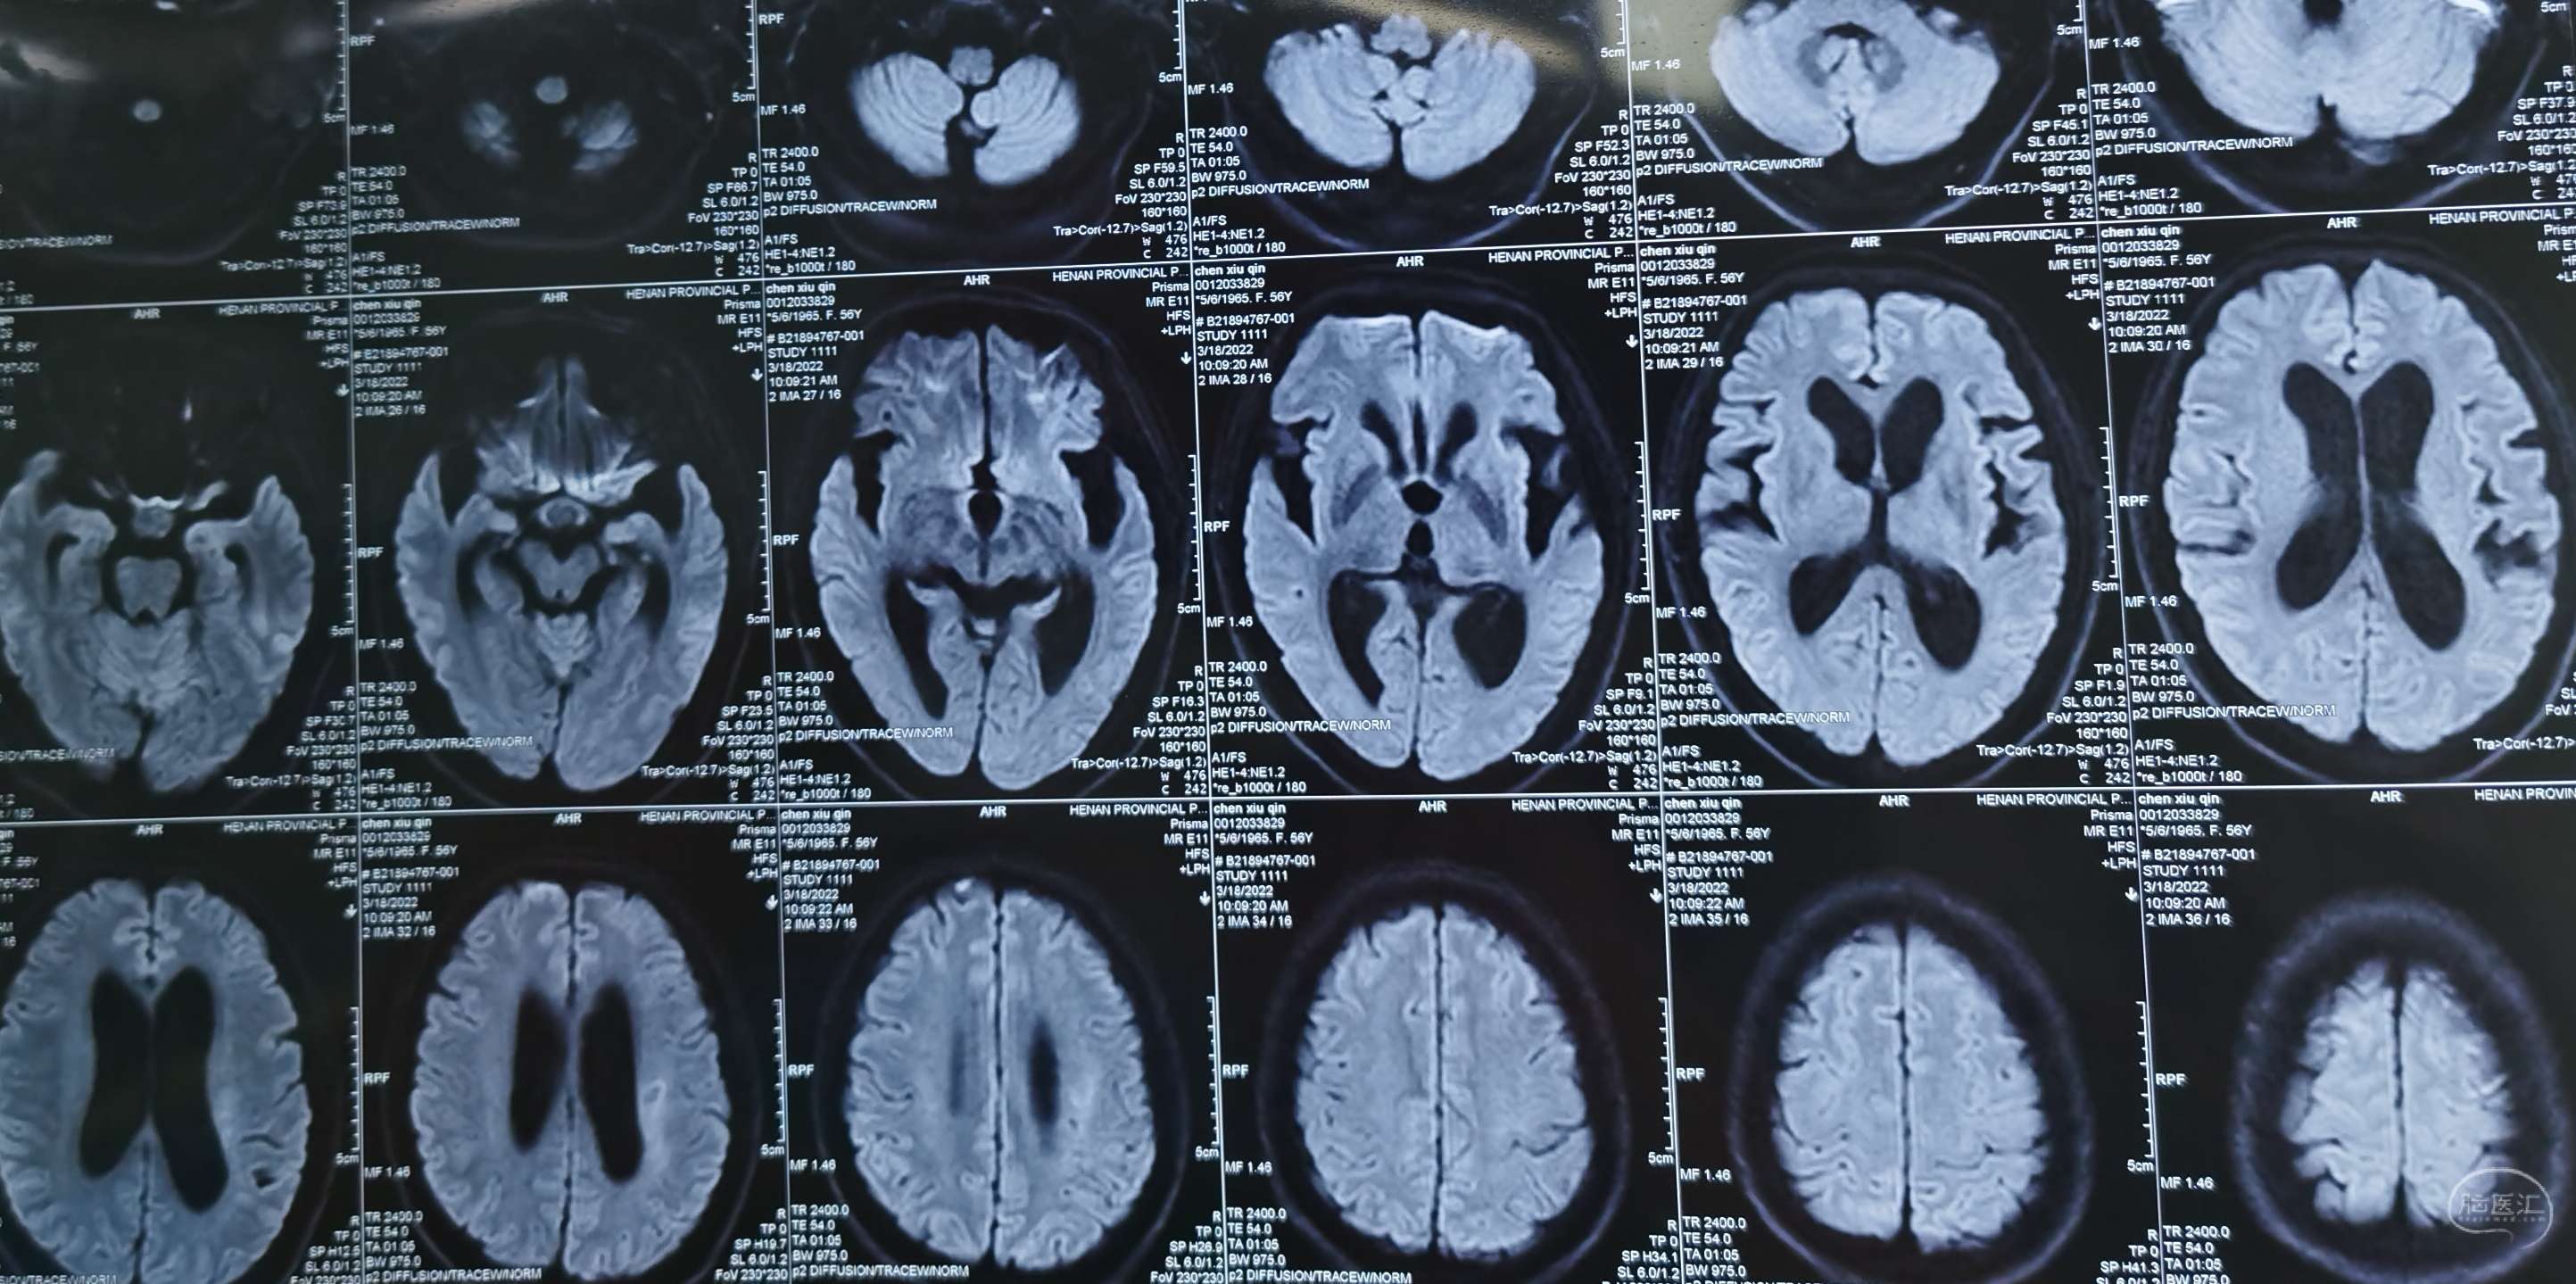

DWI:示左侧大脑半球慢性脑梗塞。脑萎缩。